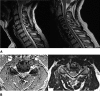

Brachioradial pruritus is a rare condition characterized by chronic localized itching of the dorsolateral upper extremities. Although the exact pathophysiology is still unknown, cervical nerve compression is thought to be a cause. We present the case of a 56-year-old man with a 6-year history of disabling chronic bilateral upper extremity pruritus and pain as well as concurrent neck pain. The patient presented to our office after multiple inconclusive diagnostic evaluations (dermatology, rheumatology, neurology, and psychiatry) and unsatisfactory multimodal conservative treatment attempts. His symptoms markedly impeded his ability to get restful sleep. Imaging of the cervical spine revealed multilevel cervical spondylosis, spinal stenosis with cord compression, and multilevel foraminal stenosis. The patient underwent successful multilevel anterior cervical decompression and fusion and was instantly symptom-free. The present case highlights that patients complaining of itching of the dorsolateral forearms of seemingly unknown etiology should undergo a workup of the cervical spine. If conservative treatment fails, surgical decompression may be considered in select patients.